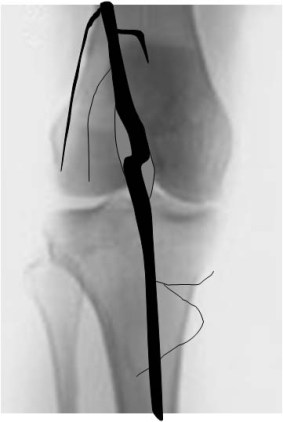

SIGNO DE LA PATA DE PERRO

Signo de aneurisma de la arteria poplítea, parcialmente trombosado, que puede verse en la arteriografía y en reconstrucciones coronales de angioTC. Consiste en una aguda angulación del recorrido de la arteria poplítea, con o sin dilatación de la luz vascular, tal como muestra el esquema.

El diagnóstico diferencial hay que hacerlo con: arteria poplítea tortuosa, ateroesclerosis poplítea, síndrome de atrapamiento de la arteria poplítea, enfermedad quística adventicial y quiste de Baker.